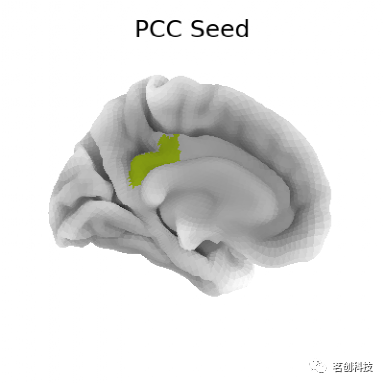

plot_surf_stat_map:绘制大脑表面的种子连接

# 提取种子的时间序列

# 从nilearn加载静息态时间序列

from nilearn import surface

timeseries = surface.load_surf_data(nki_dataset['func_left'][0])

# 通过标签提取种子区域

pcc_region = b'G_cingul-Post-dorsal'

import numpy as np

pcc_labels = np.where(parcellation == labels.index(pcc_region))[0]

# 从种子区域提取时间序列

seed_timeseries = np.mean(timeseries[pcc_labels], axis=0)

# 计算基于种子的功能连接

# 计算种子时间序列与半球所有皮层节点时间序列之间的皮尔逊积矩相关系数

from scipy import stats

stat_map = np.zeros(timeseries.shape[0])

for i in range(timeseries.shape[0]):

stat_map[i] = stats.pearsonr(seed_timeseries, timeseries[i])[0]

stat_map[np.where(np.mean(timeseries, axis=1) == 0)] = 0

# 在表面显示ROI

# 在ROI图中转换ROI指标

pcc_map = np.zeros(parcellation.shape[0], dtype=int)

pcc_map[pcc_labels] = 1

from nilearn import plotting

plotting.plot_surf_roi(fsaverage['pial_left'], roi_map=pcc_map,

hemi='left', view='medial',

bg_map=fsaverage['sulc_left'], bg_on_data=True,

title='PCC Seed')